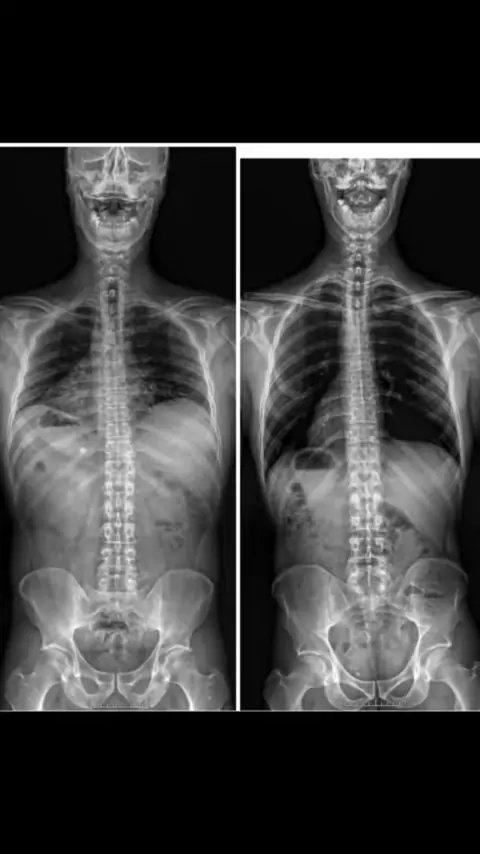

Компенсация и ее последствия #энергия#биомеханика#психосоматика#костоправ#массаж#балансздоровья#мануальныйтерапевт#причинаболезней